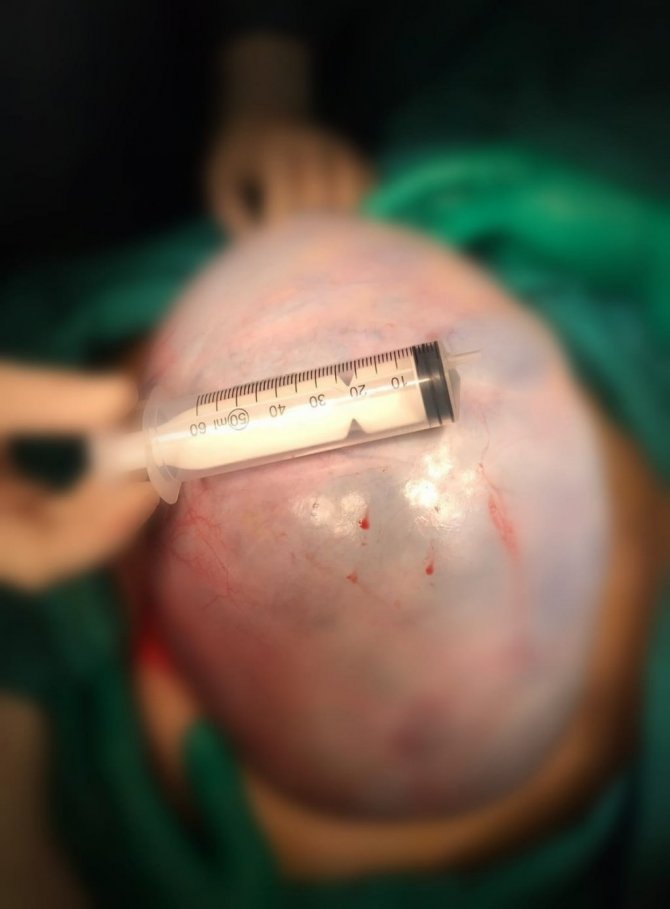

Antalya'nın Alanya ilçesinde 54 yaşındaki Havva Yılmaz, şiddetli karın ağrısı ve şişkinlik şikayetiyle başvurduğu hastanede yumurtalığında 20 kilogram ağırlığında, büyüklüğü 40 santim çapında kitle olduğunu belirlendi. Yapılan ameliyat sonrası Yılmaz, sağlığına kavuştu.

Alanya'da yaşayan Havva Yılmaz, (54) isimli şiddetli ağrı, şişkinlik ve bulantı şikayetiyle Alanya Alaaddin Keykubat Üniversitesi Eğitim ve Araştırma Hastanesine başvurdu. Yapılan tetkikler sonucu Yılmaz'ın yumurtalığında 20 kilogram ağırlığında 40 santim gelen kitle olduğunu saptandı. Yılmaz bunun üzerine Kadın Hastalıkları ve Doğum Uzmanı Op. Dr. Muhammet Serhat Yıldız ile Uzman Öğr. Üyesi Dr. Meral Tuğba Çimşir ve Op. Dr. Büşra Yıldız tarafından ameliyata alındı. Başaralı geçen ameliyat Yılmaz, sağlığına kavuştu. Bir süre normal odada kalan Yılmaz taburcu oldu.

Op. Dr. Muhammet Serhat Yıldız ise şunları söyledi: "Havva Hanımda yapılan tetkikler sonucunda abdominal bir kitle gördük. Hastamızın onayını alarak doktor arkadaşlarla birlikte ameliyat kararı aldık. Kitlenin büyüklüğü ve yeri nedeniyle operasyonun zorlu geçeceğini biliyorduk. Başından beri doğru kararlar alarak başarılı bir iş çıkardık".